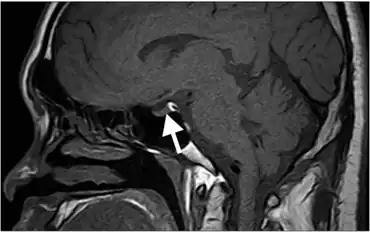

Hyperintense signal of posterior pituitary on image could not be detected, lack of this bright spot is typical of central diabetes insipidus.